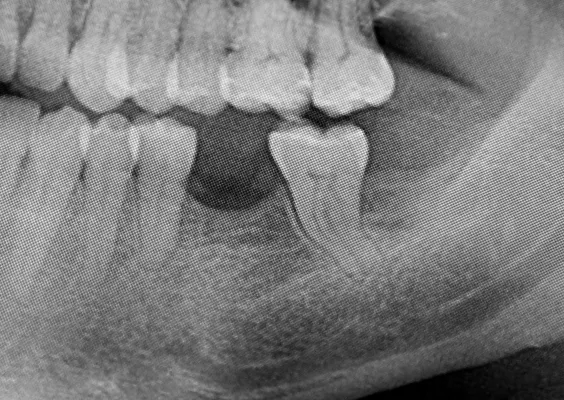

zanik kości

Zanik kości następuje w miejscach, gdzie wcześniej znajdowały się zęby, czyli w obrębie wyrostka zębodołowego szczęki oraz części zębodołowej żuchwy. Po utracie zęba brak naturalnego obciążenia mechanicznego powoduje stopniową resorpcję (wchłanianie) kości. Proces ten może prowadzić do znacznego obniżenia wysokości i objętości kości, co utrudnia późniejsze leczenie protetyczne, np. wszczepienie implantów.

ODBUDOWA UBYTKU PO USUNIĘCIU ZĘBA - SOCKET PRESERVATION

To prosta, szybka i bezpieczna technika odbudowy kostnej zębodołu po ekstra-kcji zęba. Znana wcześniej, lecz opisana dopiero w ramach międzynarodowego konsensusu z 2010 roku (prof. Lindhe, prof. Araujo)

Zabieg odbudowy zębodołu powinno się wykonać możliwe jak najszybciej po usunięciu zęba. Jego celem jest odbudowa naturalnej objętości kości w miejscu utraconego zęba, a następnie szybkie wprowadzenie implantu. Najlepsze rezul-taty uzyskuje się przy zastosowaniu biomateriału w formie bloczków kolageno-wych lub granulatu, które dają trwałe efekty odbudowy oraz optymalną funkcję i estetykę odtworzonych koron zębów na wszczepionym implancie.